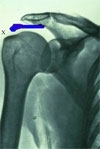

Normalny wygląd przyczepu mięśnia nadgrzebieniowego (m.supraspinatus), z lewej strony ścięgno mieśnia dwugłowego (m.biceps brachii), na dole głowa kości ramiennej. Na zdjeciu rentgenowskim na niebiesko.

Zerwanie całkowite przyczepu (X).